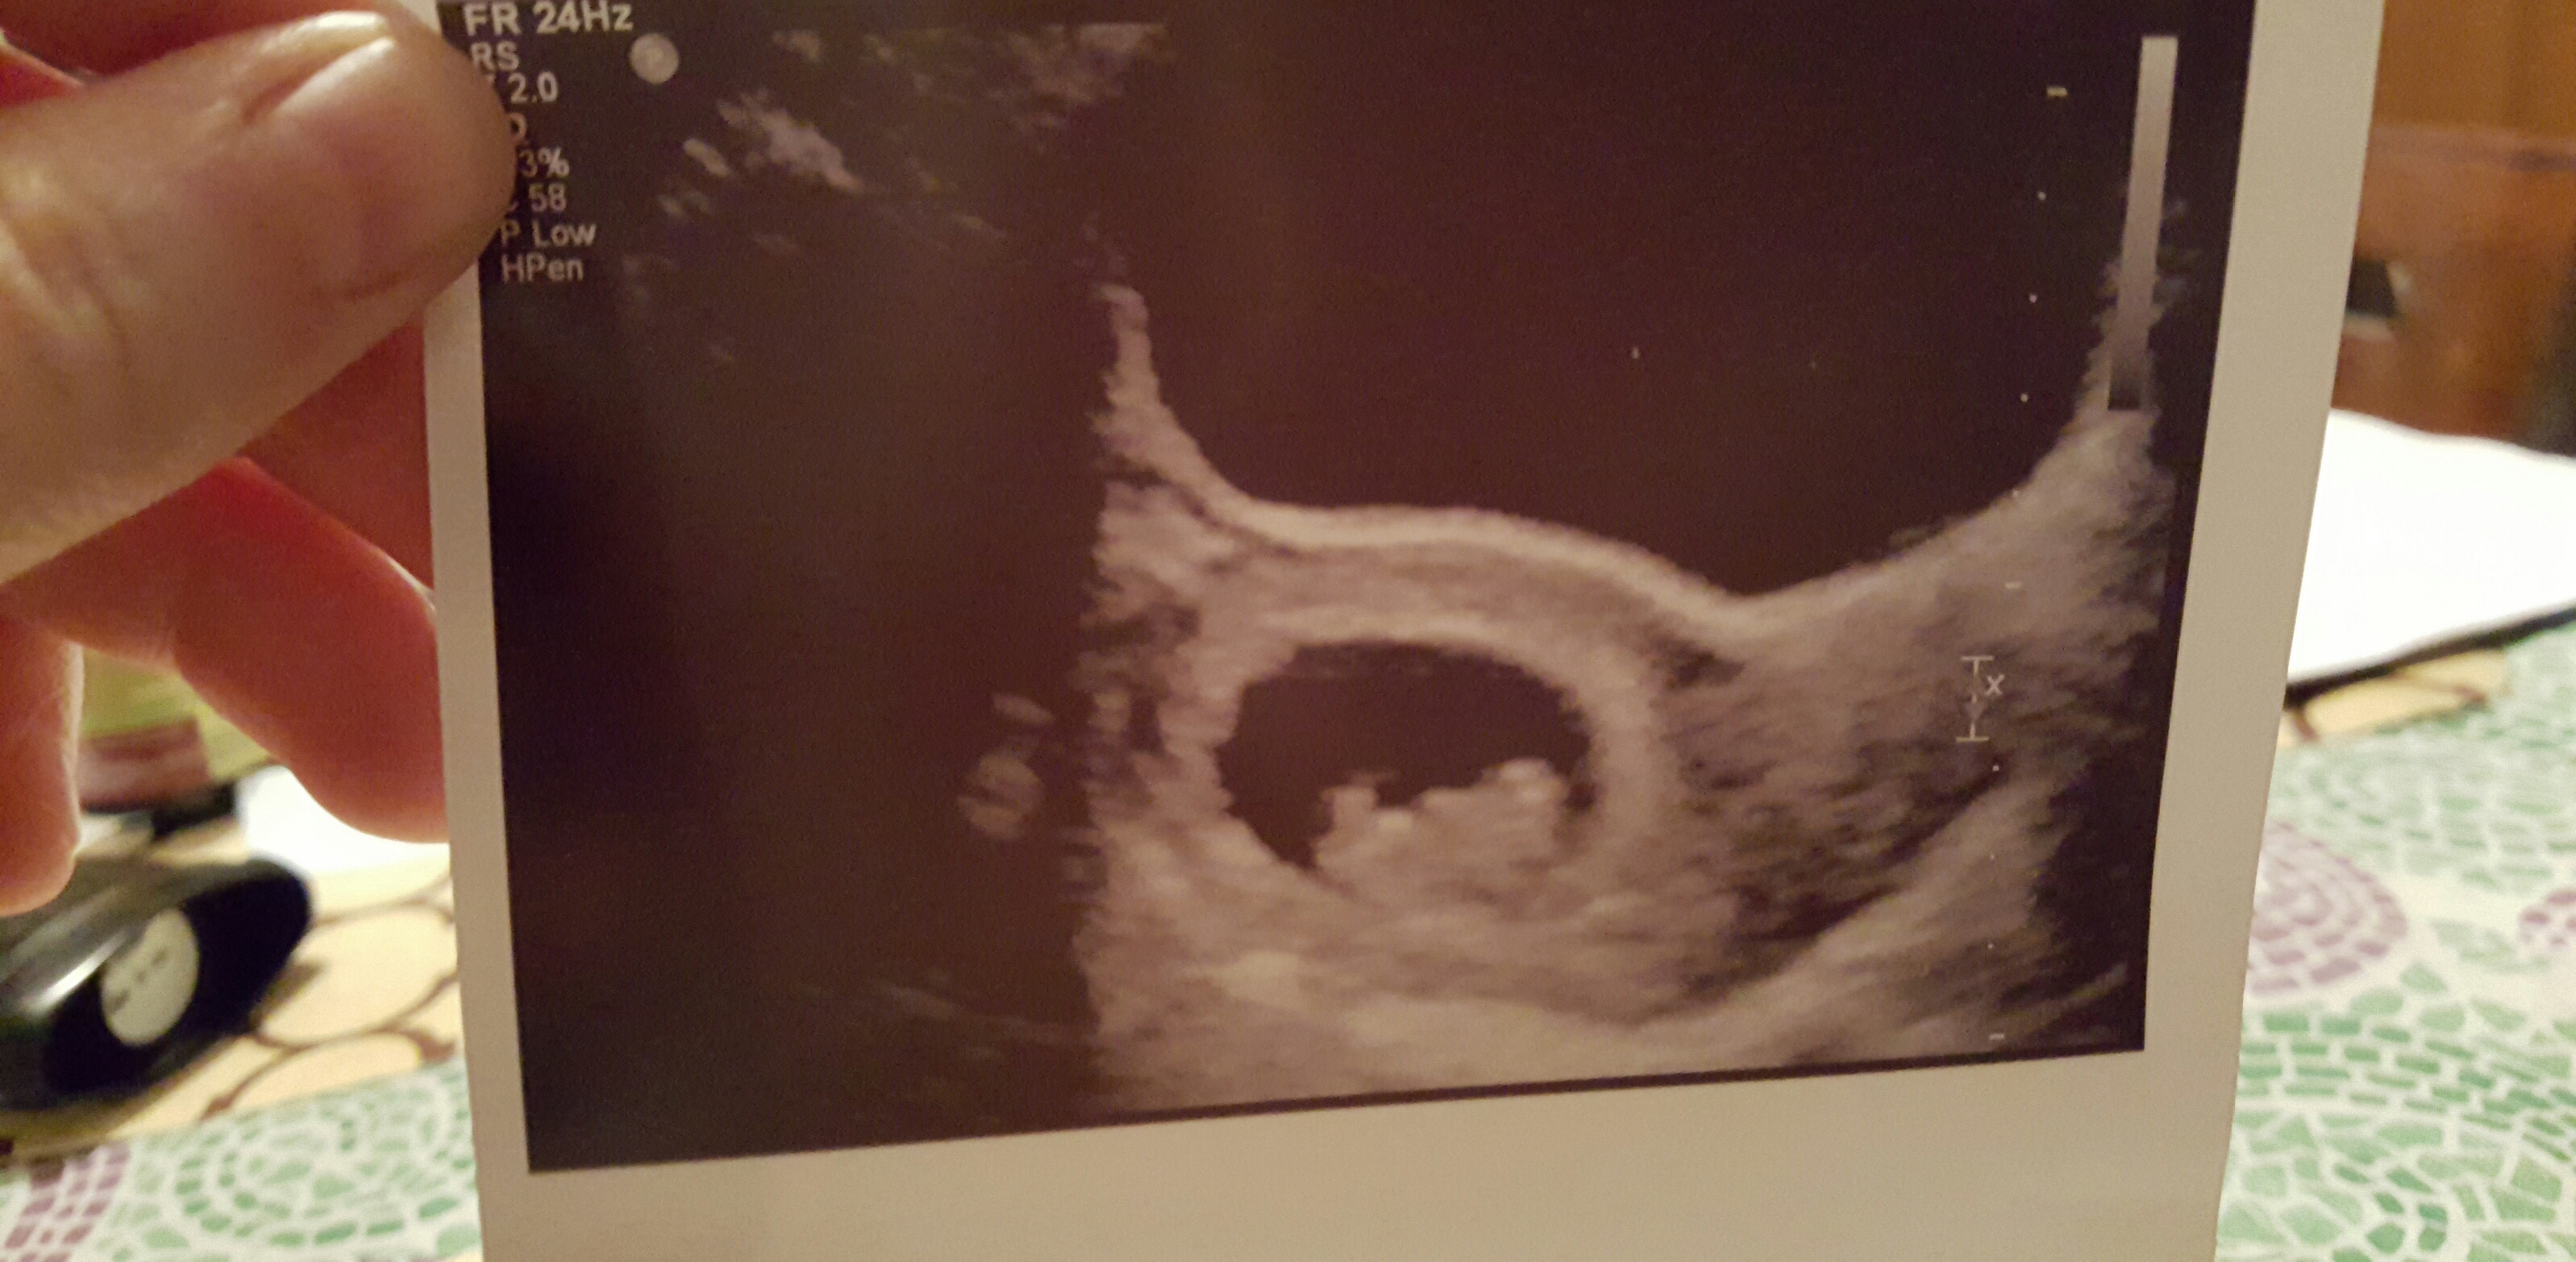

So, my lobster was 6 days behind but everything looks perfect. Late implantation seems to be the cause and that happened with my first pregnancy, too. It's probably a boy.

6w4d. Heartbeat at 140. Tech said ultrasound was messing up a bit, which could explain the "mirror twin". Guess we have to wait and see! (Anyone else have this issue?)

Tech said ultrasound was messing up a bit, which could explain the "mirror twin". Guess we have to wait and see! (Anyone else have this issue?)

Not a great photo, but we saw the little flicker of the heartbeat!